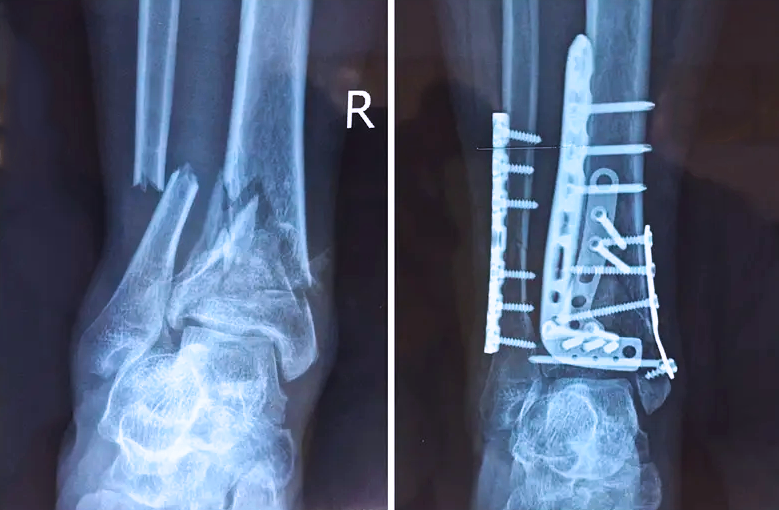

對(duì)于骨科醫(yī)生而言,關(guān)節(jié)外的骨折是相對(duì)比較簡單的,因?yàn)殛P(guān)節(jié)外的骨折允許我們復(fù)位的時(shí)候有一些偏差,但是如果骨折部位在關(guān)節(jié)內(nèi),我們就不能有任何的偏差。而且關(guān)節(jié)內(nèi)的骨折是有關(guān)節(jié)面的,如果關(guān)節(jié)面不平整,就會(huì)導(dǎo)致患者以后出現(xiàn)創(chuàng)傷性關(guān)節(jié)炎等癥狀,或者出現(xiàn)長時(shí)間的疼痛,甚至造成殘疾。所以對(duì)于關(guān)節(jié)內(nèi)的骨折,一定要做到“解剖復(fù)位”,就像搭積木一樣,每個(gè)積木塊、每個(gè)碎骨塊都要完好的拼到一起,做到嚴(yán)絲合縫。

踝關(guān)節(jié)是人體中負(fù)重較大的關(guān)節(jié),也是活動(dòng)度較大的地方,所以對(duì)于足踝部位的關(guān)節(jié)內(nèi)骨折,我們更需要做到“解剖復(fù)位”。對(duì)于這種關(guān)節(jié)內(nèi)的骨折,尤其是踝關(guān)節(jié)內(nèi)部的骨折,不僅需要進(jìn)行X影像平片正側(cè)位的拍攝,由于在二維影像上無法判斷關(guān)節(jié)面的受損情況,往往還需要進(jìn)行三維影像的檢查。

在術(shù)前,我們需要做三維掃描的CT檢查,我們必須要有CT的片子,還要有三維的重建。

在術(shù)中,我們?cè)趺慈ヅ袛嚓P(guān)節(jié)面平不平整呢?常規(guī)的正側(cè)位影像是不能判斷的。有些醫(yī)生為了準(zhǔn)確的判斷,可能會(huì)選擇做開放性的手術(shù),把關(guān)節(jié)暴露出來,在眼睛的直視下判斷關(guān)節(jié)面平不平整。但是關(guān)節(jié)全部打開,無疑增加了病人的創(chuàng)傷,而且增加了患者的恢復(fù)時(shí)間。所以如果在術(shù)中我們有三維影像的支持,對(duì)醫(yī)生做手術(shù)而言就會(huì)事半功倍,而且能夠大大的增加手術(shù)準(zhǔn)確度,增加患者術(shù)后的預(yù)后。所以在術(shù)中有三維影像的支持是非常必要的!

三維影像? 看透關(guān)節(jié)內(nèi)骨折的“眼睛”